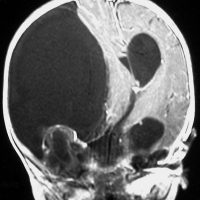

生後5ヶ月の女児に発生した右中頭蓋窩から海綿静脈洞から側頭下窩の成熟奇形腫です。腫瘍のう胞が大きく,右大脳半球の高度の圧排変形がみられます。

のう胞が巨大なので,まずのう胞腹腔シャントをして脳の変形を戻しました。その2ヶ月後に開頭手術で腫瘍を亜全摘出しています。

小児科から抗てんかん薬の投与を受けていますが学習障害などなくて正常です。また腫瘍再発もなく,看護学校へ通学しています。